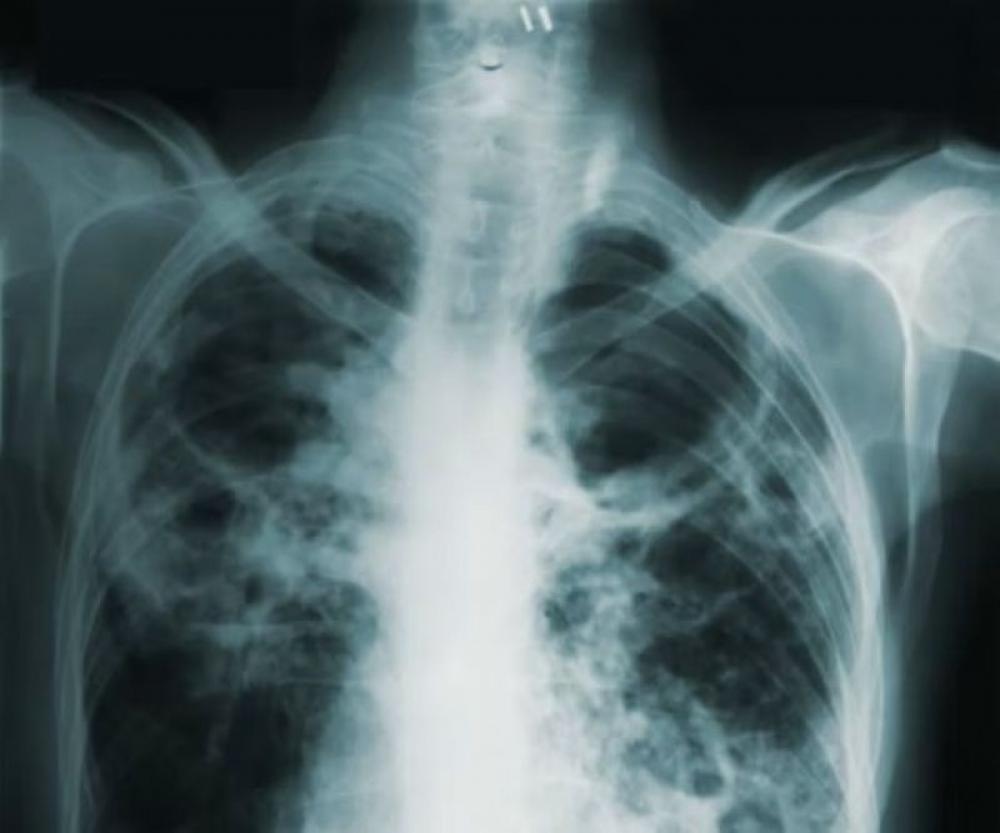

TB Pulmonary tuberculosis. Photo: Unsplash

TB is caused by bacteria that most often affects the lungs. Every day, over 3,300 people die from the disease, with Southeast Asia accounting for nearly 40 per cent of deaths. Yet it is both preventable and treatable, including by using the antibiotic rifampicin.